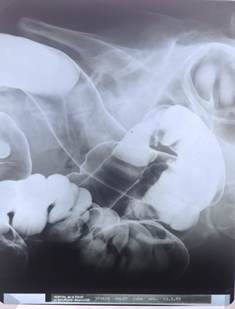

X-rays are a form of electromagnetic radiation which are emitted when a tungsten target is bombarded with fast electrons in a vacuum tube. They have an extremely short wavelength which means that they can pass through most substances, including human soft tissue, casting shadows of solid objects in their path, such as metal and bone.

The news of Roentgen’s discovery spread quickly throughout the world. One of his first experiments late in 1895 was a film, or shadowgraph, of his wife Bertha’s hand with a ring on her finger. Of all the first pictures of his that were circulated it was that of the human hand that made the greatest impression upon the public. Everywhere people began testing the new radiation by taking pictures of the bones in their hands.

Until the x-ray, all knowledge of human anomalies (apart from visible ones) was limited to those found by anatomists at dissection. But now, new living anatomy was being shown on radiographs.

As this different view of the body came about, the interpretation of shadows had to be made with care. Early radiologists were like aircraft spotters.[ix] Abnormalities of forensic importance were (still are) often subtle and the shadows cast by the new rays could often be confusing. And, of course, what was normal?